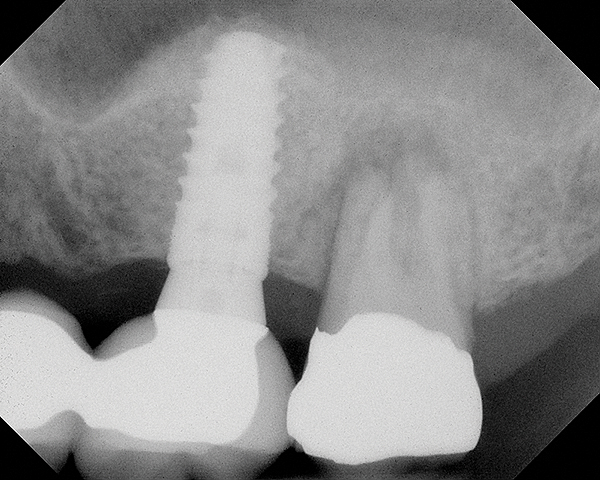

As with implant placement in general, use of a round bur is the first step in forming the osteotomy. As described above, to get verification of positioning—especially if a surgical stent is not used—a small piece of gutta percha can be placed inside this small osteotomy and a radiograph taken (Figure 1), after which the gutta percha is removed. The next step is the most critical, as it involves exposing the Schneiderian membrane. A 2-mm twist drill is used at a speed not exceeding 250 rpm, using a very light touch. Because the bone quality in the maxillary posterior is generally poor, it is usually easy to feel when the medullary bone has been breached and the dense cortical bone of the floor of the sinus has been reached. The cortical plate of the floor of the sinus should have been carefully measured with periapical radiographs presurgically, but it is usually about 1 mm in thickness. The most important and technique-sensitive part of this procedure is breaching the cortical plate of bone lining the sinus without tearing the sinus membrane. With a solid finger rest, good control, very light drilling pressure, copious irrigation, and a slow drilling speed, a slight “give” occurs once this plate of bone is breached. The full width of the twist drill should not penetrate the sinus floor; otherwise, the membrane will be torn. If it is not clear whether the membrane has been exposed, a flat-ended implant probe (Figure 2) can be used by inserting it into the osteotomy and feeling for the slight “give” or movement of the membrane. If the surgeon is not sure if the membrane is exposed, a radiographic marker can be used (Figure 3). If the membrane is significantly exposed, however, a radiographic marker should not be used, as this can inadvertently tear the membrane. The patient should also be warned not to bite down on the marker during the radiograph to avoid a membrane tear, and floss must be attached to the marker, so it can be retrieved if necessary.

Fig 1. Radiograph of gutta percha placed at the base of the initial osteotomy with a round bur to verify location.

Figure 1